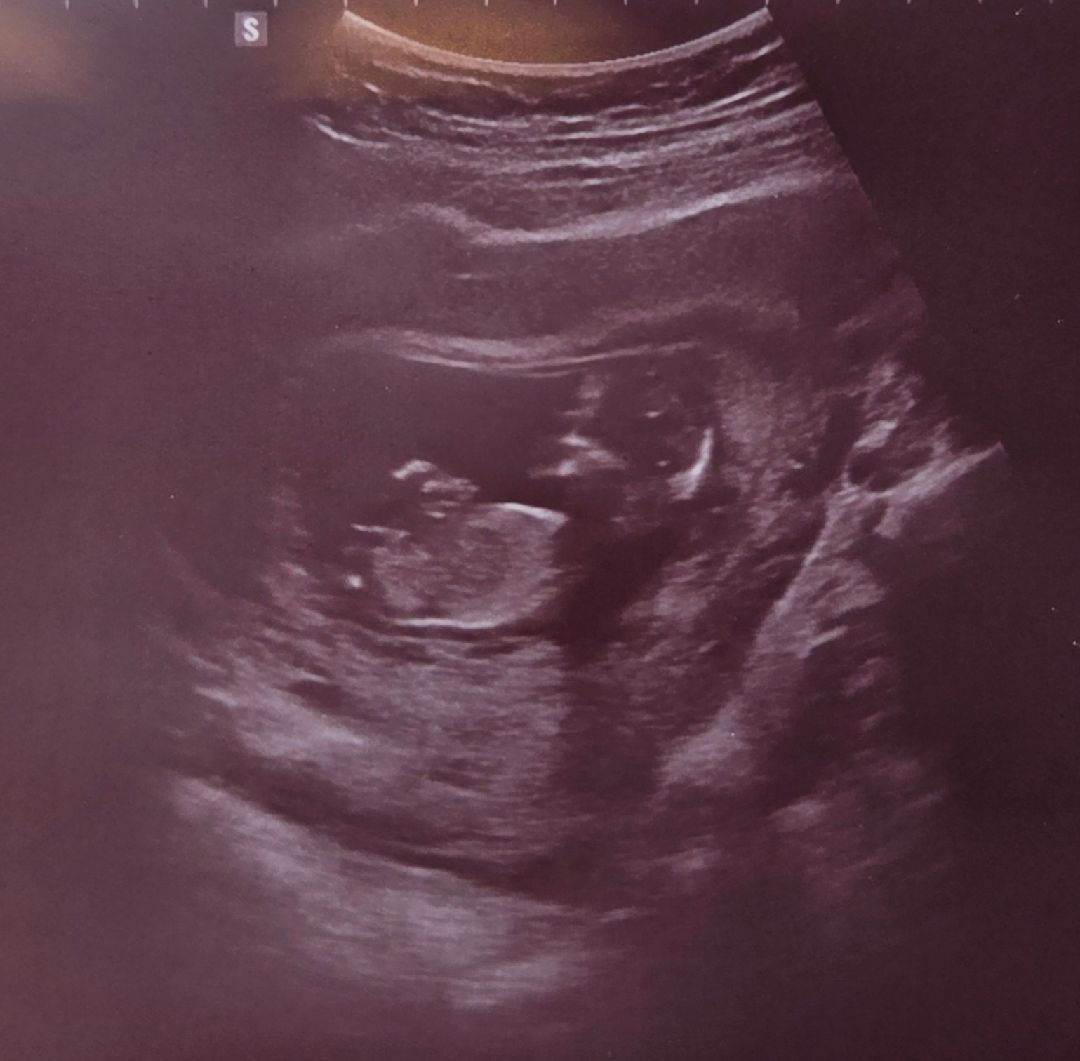

11주 6일 차 입니다 혹시 성별이 어떻게될까요